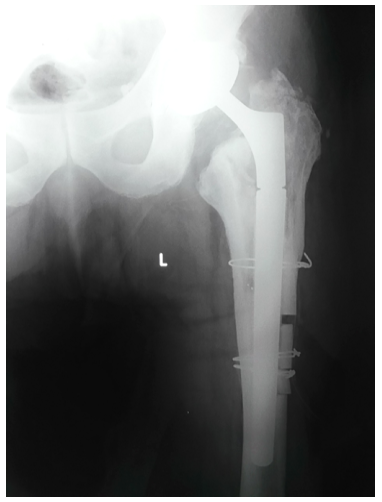

The patient is a 61-year-old, Caucasian man measuring 180cm in height and 100kg in weight, with body mass index of 30.86 (BMI). He was diagnosed with a bilateral hip osteoarthritis and admitted to our Department in November 2009 when total hip arthroplasty (Lima SPH-ST/C2, Lima International, Udine, Italy) of the right hip was performed. Subsequent total hip arthroplasty (Lima SPH-ST/C2, Lima International, Udine, Italy) of the left hip was performed in November 2010 (Figure 1). The patient underwent regular ambulatory controls with clinical and radiology examinations. Because of the aseptic loosening of femoral stem (stem subsidence) a revision surgery was made in February 2014. Revision femoral stem was implanted (Lima revision, Lima International, Udine, Italy) (Figure 2) using trans femoral approach according to Wagner in the lateral decubitus position.9 Femoral component was a cementless modular porous-coated stem made of titanium alloy with distal anchoring (tapered, fluted). Size of femoral stem was 22x140mm with the proximal part length of 70mm (total stem length 210mm). Postoperative course was without complications. Patient felt a sudden sharp pain in his left hip while walking in October 2015, 20 months after the revision procedure. Limping and the pain in left hip were increasing daily. He presented to our Department with the leg held in the external rotation and with decreased movements in hip joint. Plain radiograph showed a fracture of the revision femoral component of the left hip (Figure 3). The patient underwent a planned revision surgery procedure. Trans femoral approach according to Wagner was used again.9 Fracture was found at a junction between proximal and distal part of the stem (Figures 4 & 5). Extraction of the distal part of the stem was performed using technique developed at our Department.10 Proximal part is easy to extract without any complications. Problem is with distal part that is firmly fixed in the bone. It was removed with a special longitudinal osteotomy through the anterior cortex extending distally for 15cm. It was then followed by a transversal osteotomy 2cm below the tip of the femoral stump to allow enough space for two locking pliers. Simultaneously using a lamina spreader on the distal part, the broken stem was extracted while hammering on two locking pliers. Cementless revision femoral stem was implanted in a standard manner (Figure 6).

Figure 3 Plain radiograph of fractured modular femoral stem.